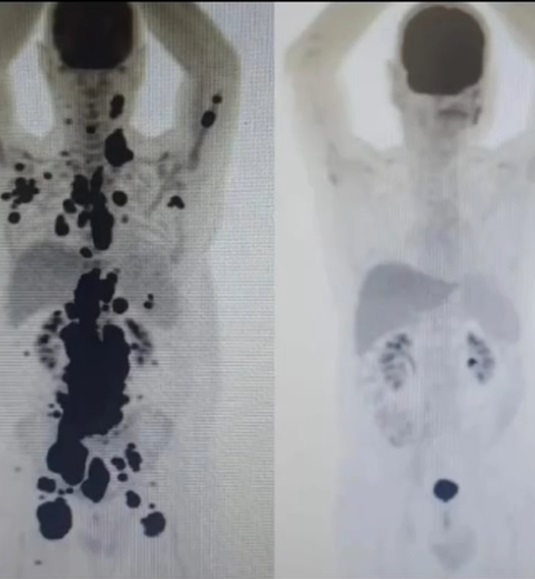

O homem realizou um Pet Scan, tomografia feita com um contraste especial, no dia 22 de abril e o resultado saiu nesta última sexta-feira (3).

“Estou celebrando mais um passo em direção à cura justamente no aniversário de quem foi fundamental aqui na terra para essa caminhada continuar. Mais um Pet Scan confirmando a remissão de 100% dos meus cânceres, graças a Deus, isso depois de dias de atraso do laboratório, que nunca havia acontecido antes”, declarou ele em vídeo postado nas redes sociais.

O resultado saiu justamente no aniversário do médico que tratou Paulo. “Até que o laudo saiu no dia do aniversário do doutor Vanderson Rocha, meu médico. Coincidência? Não acredito nisso há muito tempo. Como disse ao doutor Vanderson, é o meu presente de aniversário para ele, ou seja, para nós. Um passo, ou melhor, um Pet Scan de cada vez”, seguiu.